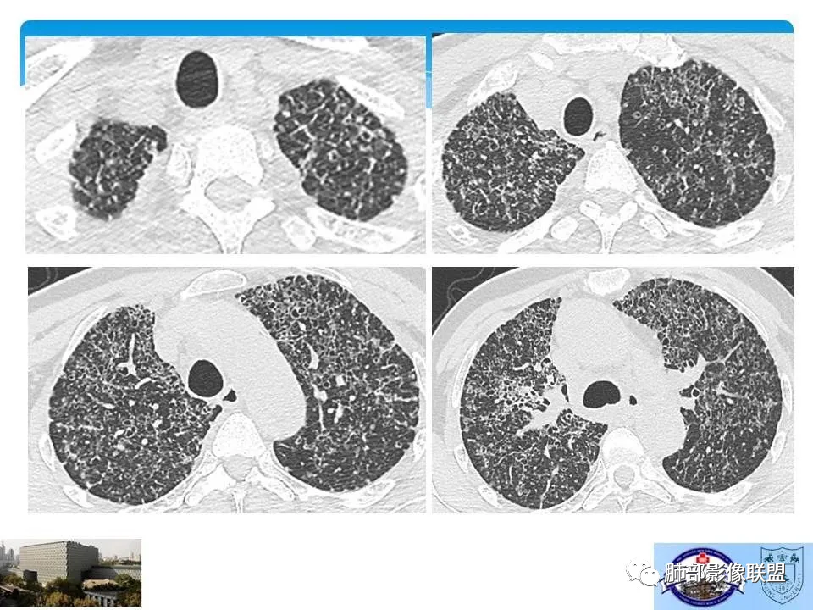

中年女性,不吸烟

双肺弥漫囊腔,累及肋膈角,囊腔形态相对规则单一。

符合LAM

CT平扫示双肺弥漫分布大小不等囊状薄壁透光区,无内、中、外带分布差异,间质稍示增厚。拟LAM

中年女性育龄期妇女,咳嗽气喘,无吸烟史,有苯吸入史。影像:双肺弥漫均匀小囊腔,无明显分布优势,囊腔形态欠规则,壁薄,部分囊腔边缘血管征,伴双肺弥漫磨玻璃影,无结节,考虑lam,鉴别苯中毒肺损伤,囊腔多有分布优势,小叶中心分布为主,形态规整等

女,46,活动性气喘1年。苯吸入史半年。胸部CT:两肺弥漫囊腔,上至肺尖,下至肋膈角,形态类似小囊腔。考虑:LAM,鉴别LIP,BHD,PLCH等。

CT表现:双肺弥漫大小不等的薄壁囊腔,囊壁<2mm,外形规则,血管影多位于囊腔周围,囊腔之间肺组织正常,随着疾病进展到晚期,囊腔变大、增多,不可胜数,囊腔可融合成较大的囊,与肺气肿相似,形成间质性肺纤维化。部分病例可出现结节影。